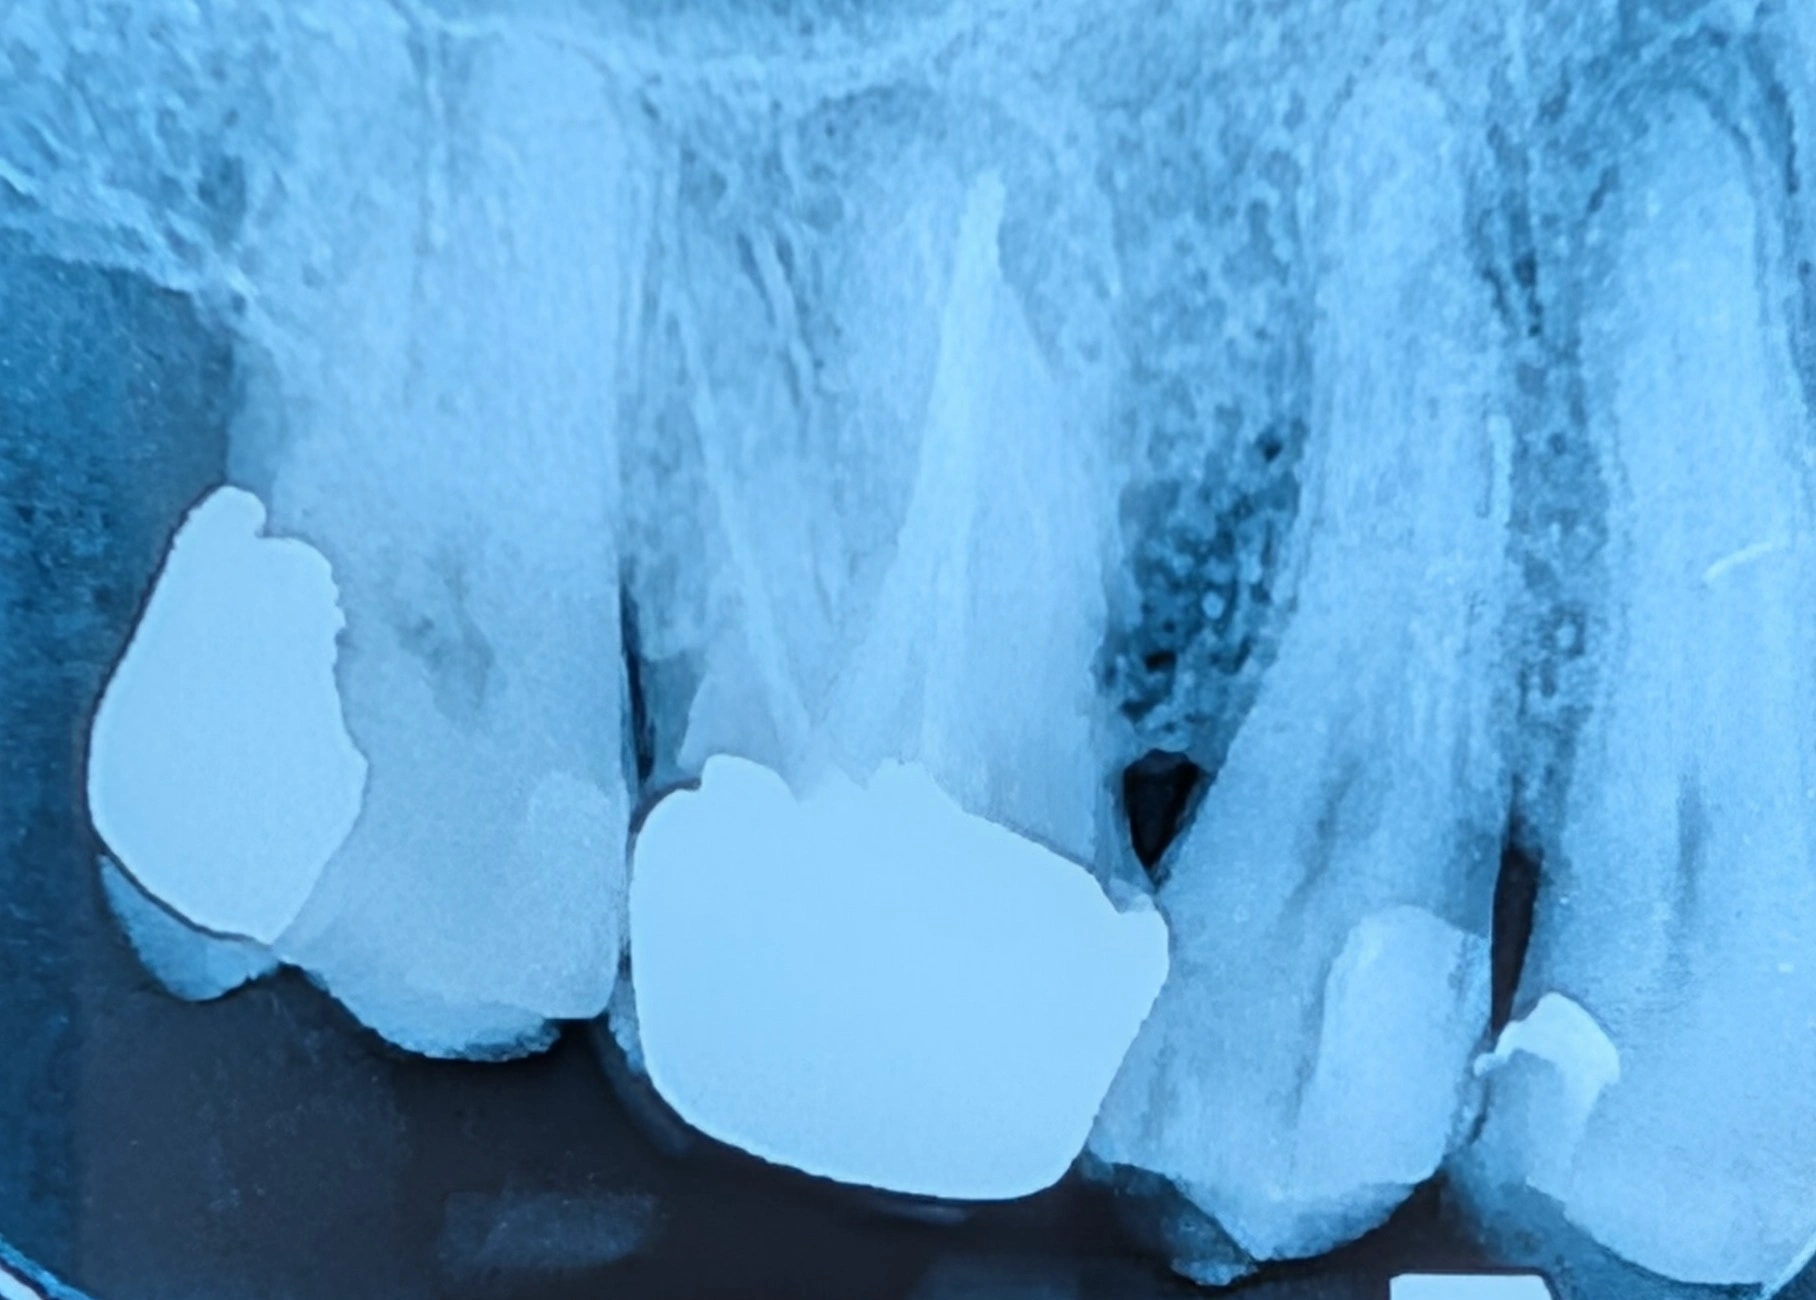

رادیوگرافی PA دندان‌های خلفی

نمای دقیق‌تر دندان‌ها در رادیوگرافی PA

عکس‌های کوچک دندانی مانند PA یا بایت‌وینگ روی چند دندان مشخص تمرکز دارند و جزئیات بسیار دقیق‌تری نشان می‌دهند.

به همین دلیل، این تصاویر بهترین روش برای تشخیص پوسیدگی‌های بین دندانی و بررسی مشکلات ریشه دندان محسوب می‌شوند.

نمونه مقایسه در این بیمار

در تصاویر مربوط به دندان‌های ۴، ۵ و ۶ فک بالا، در عکس پانورامیک ناحیه بین دندان‌ها واضح دیده نمی‌شود، اما در تصویر PA همان ناحیه با جزئیات بیشتر قابل مشاهده است و تشخیص پوسیدگی با دقت بالاتری انجام می‌شود.